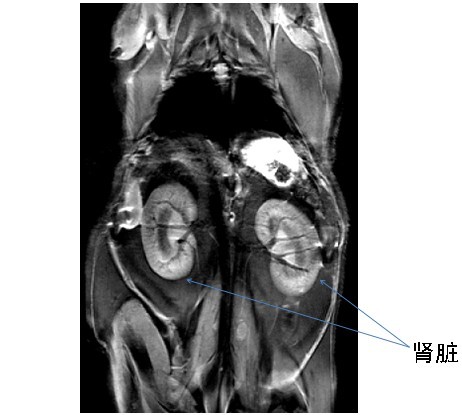

高脂饮食小鼠的脂肪抑制肾脏高分辨率MR图像